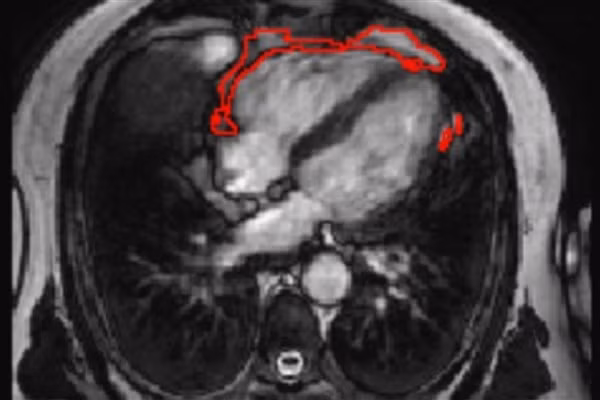

Một ví dụ về các chất béo tích tụ được phát hiện bởi công cụ mới.

Tuy nhiên, đến nay, vẫn chưa có phương pháp nào đơn giản giúp đo lường tình trạng này. Các nhà khoa học đã phát triển một công cụ trí tuệ nhân tạo, nhằm định lượng các chất béo tích tụ từ hình ảnh MRI thông thường.

“Để giải quyết vấn đề này, chúng tôi đã phát minh ra một công cụ AI có thể được áp dụng cho cộng hưởng từ MRI với tim. Nhờ đó, giúp đo lượng mỡ xung quanh tim tự động và nhanh chóng, trong vòng chưa đầy 3 giây”, Zahra Raisi-Estabragh - Trưởng nhóm nghiên cứu, cho biết.

Sau khi đào tạo một mạng nơ-ron mới, độ chính xác của công nghệ được đánh giá bằng cách sử dụng một số bộ dữ liệu độc lập. Các nhà nghiên cứu xác nhận, công cụ này thực sự có thể đo chính xác tổng khối lượng PAT từ hình ảnh MRI tim.